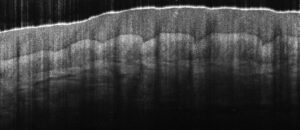

Better roll-off performance and greater camera sensitivity enables visualization of deep vasculature in the dermis.

Imaging of the full anterior chamber is possible with the 12 mm imaging depth of our newest Cobra-S model.